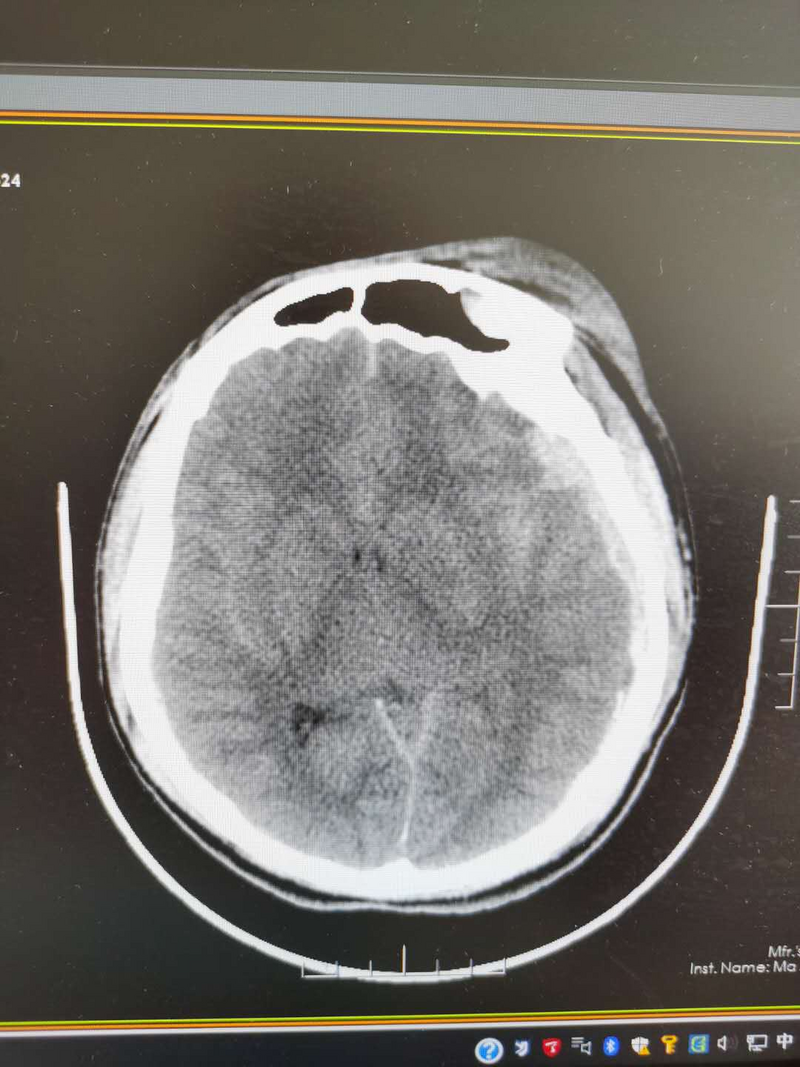

時間就是生命。神經(jīng)外科醫(yī)護(hù)人員立即完善術(shù)前準(zhǔn)備,急診開顱手術(shù)。經(jīng)過4個多小時的緊張手術(shù),患者終于轉(zhuǎn)危為安。術(shù)后患者轉(zhuǎn)入ICU繼續(xù)搶救,在神經(jīng)外科、ICU、胸心外科的共同努力下,患者順利渡過了腦水腫、再出血和感染的危險期。術(shù)后10天由ICU轉(zhuǎn)回神經(jīng)外科病房進(jìn)一步治療。

在神經(jīng)外科醫(yī)護(hù)人員的精心治療下,患者神志清醒,認(rèn)知功能正常,言語功能基本正常,可下地行走。9月11日痊愈出院。出院那天,他懷著感激之情,向給了他第二次生命的醫(yī)護(hù)人員依依告別,乘上返鄉(xiāng)的列車。